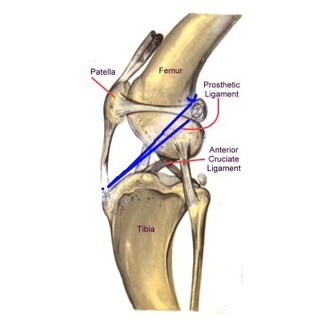

- Sutura Laterale: il mezzo più comune di stabilizzare il legamento crociato anteriore è la sutura laterale. Si tratta di una tecnica extracapsulare il cui scopo è quello di stabilizzare e sostituire alla funzione del legamento crociato craniale quella di un legamento artificiale in nylon posto tra fabella e cresta tibiale. Una valida ed economica soluzione, soprattutto in soggetti non molto pesanti e non destinati ad attività fisica spinta.

- Tightrope: è una tecnica recente, non richiede il taglio di osso come la TPLO o TTA. Sfrutta dei punti isometrici a livello di tibia e femore in cui vengono realizzati dei tunnel in cui all'interno passa un biomateriale sintetico per fornire la stabilizzazione.